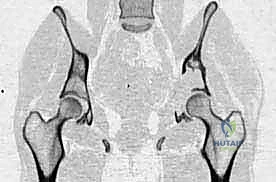

- التصوير المقطعي المحوسب (CT Scan): يقدم صوراً ثلاثية الأبعاد تُظهر بدقة متناهية مدى تدمير القشرة العظمية، وهو الفحص الأهم للتخطيط الجراحي وتحديد خطر حدوث الكسور المرضية.

- التصوير بالرنين المغناطيسي (MRI): الفحص الأفضل لتقييم امتداد الورم خارج العظم إلى الأنسجة الرخوة (العضلات، الأوعية الدموية، الأعصاب) وتقييم مدى إصابة نخاع العظم.